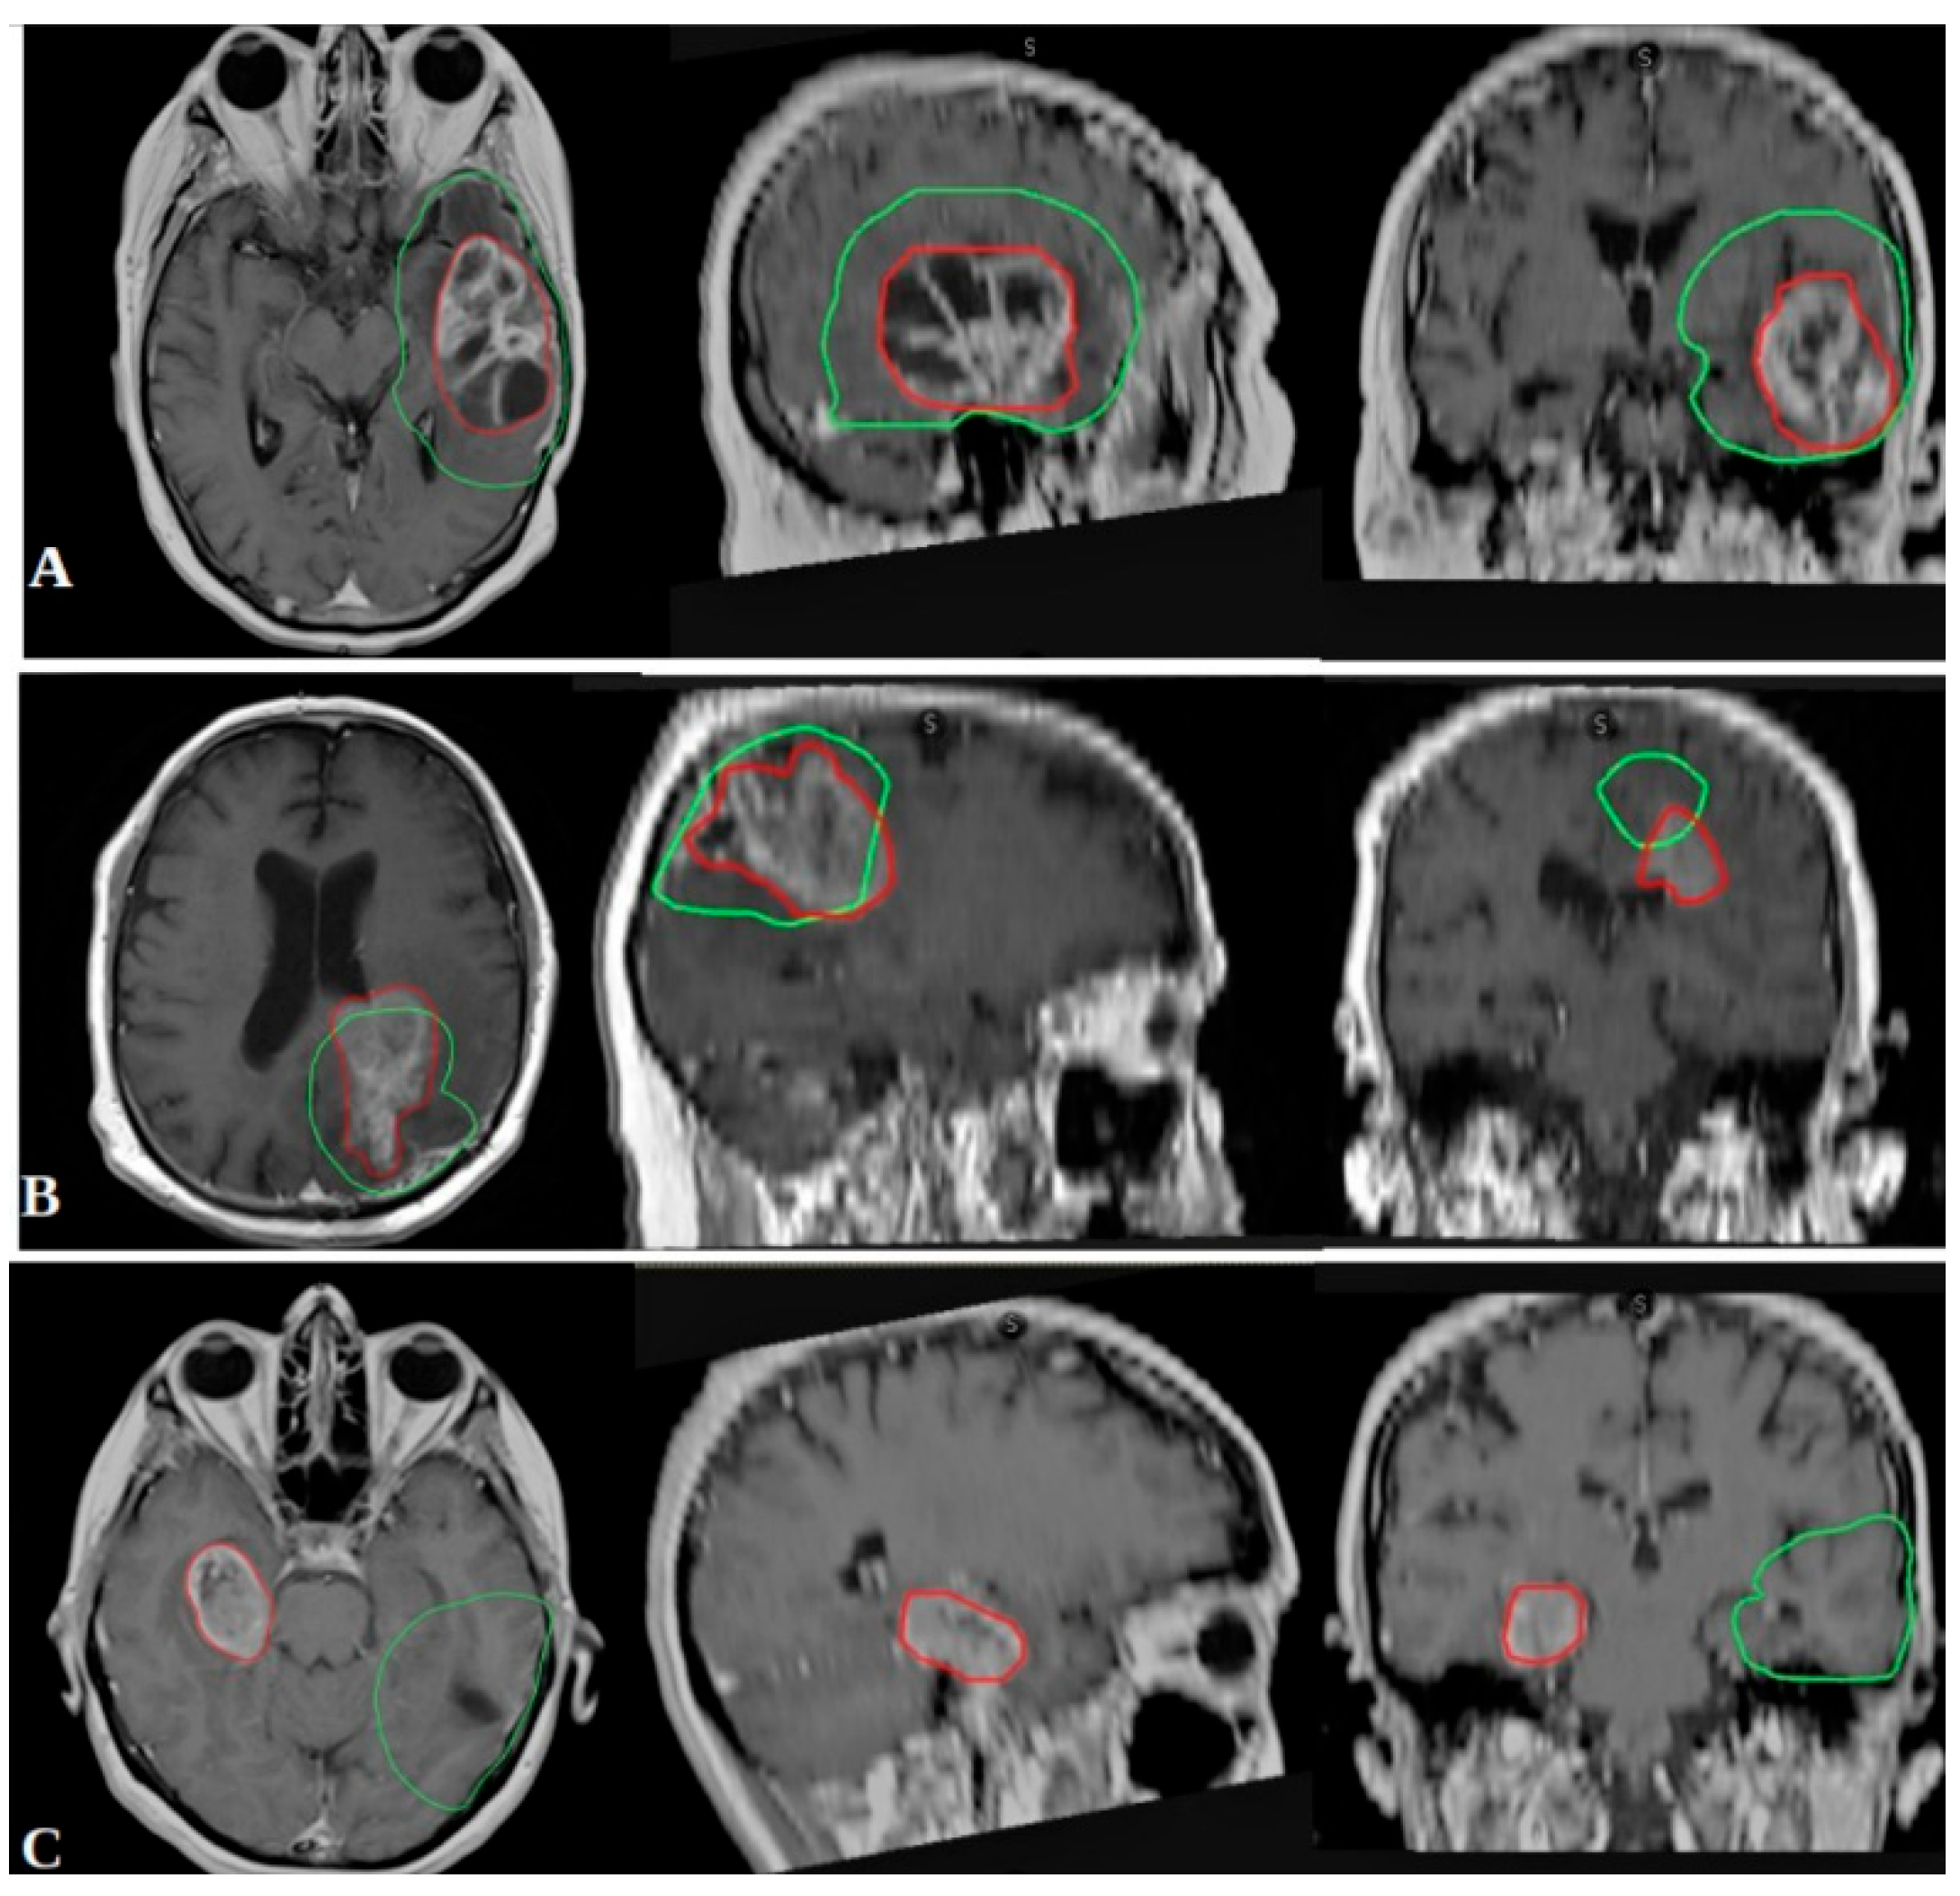

2.2. Outcome Measures and Recurrence Classification

- In-field recurrence: ≥80% of the recurrent tumor volume within the 95% isodose line.

- Marginal recurrence: 20–80% of the recurrent volume within the 95% isodose line.

- Out-field recurrence: <20% of the recurrent volume within the 95% isodose line.

3.4. Recurrence Patterns and Correlation with Biomolecular Markers

| Biomarker Group (EGFR/MGMT) | In-Field Recurrence (%) | Marginal Recurrence (%) | Out-Field Recurrence (%) | TOT |

|---|---|---|---|---|

| EGFR neg/MGMT met | 30 (81.1%) | 1 (2.7%) | 6 (16.2%) | 37 (100%) |

| EGFR neg/MGMT unm | 23 (82.1%) | 2 (7.2%) | 3 (10.7%) | 28 (100%) |

| EGFR iper/MGMT met | 26 (56.5%) | 6 (13.1%) | 14 (30.4%) | 46 (100%) |

| EGFR iper/MGMT unm | 47 (71.2%) | 16 (24.2%) | 3 (4.6%) | 66 (100%) |